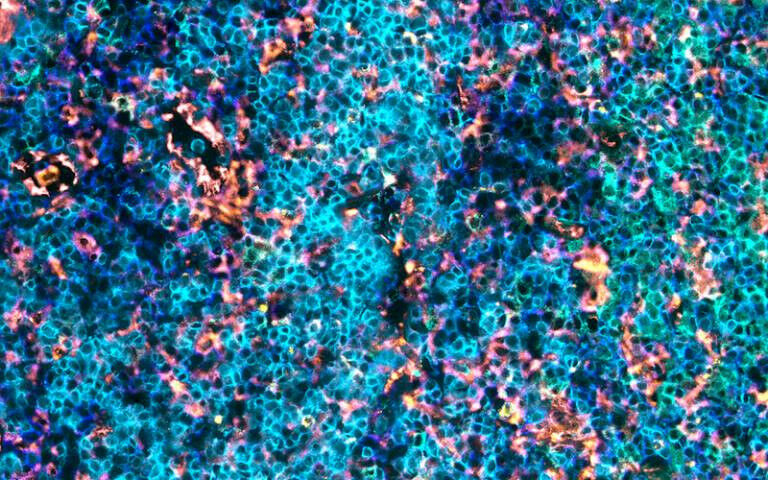

winning - A series of captivating images from UCL researchers have been showcased as part of an image competition called 'A moment of research'. Staff from across UCL Great Ormond Street Institute of Child Health (UCL GOS ICH) and GOSH including the National Institute for Health Research Great Ormond Street Hospital Biomedical Research Centre (NIHR GOSH BRC) were invited to submit images that highlighted any aspect of their life-changing research that helps find treatments and cures for some of the most complex illnesses, transforming the lives of seriously ill children both in the UK and across the world. These ranged from beautiful microscopy to intricate representations of data and photography. The winning image, 'Leukocyte Kaleidoscope' entered by PhD candidate Christina Burke (UCL GOS ICH) shows immune cells in the tonsil tissue. Among the blues and pinks are T- cells, which play an important role in fighting cancer. Those surrounded by a yellow ring are at risk of becoming over-stimulated, or 'exhausted'. Christina's team are looking at images like this to better under how T-cells interact with other cells within a tumour.